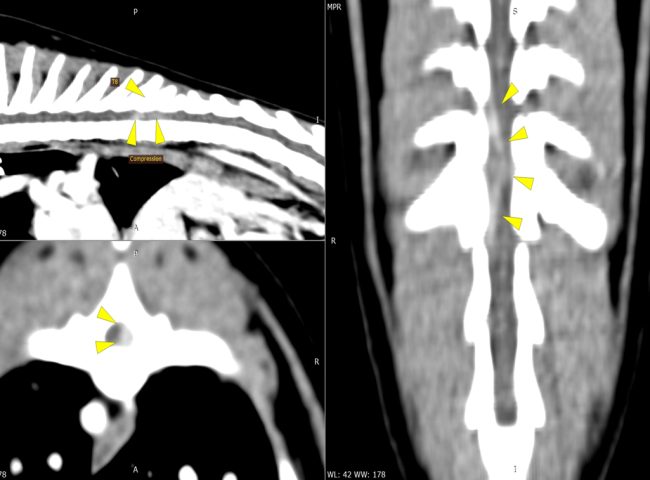

Hernie thoracolombaire sur un Teckel.

À gauche, reconstruction scanner multiplanaire mettant en évidence une hernie discale T13–L1 latéralisée à gauche, responsable d’une compression focale de la moelle épinière.

Au centre, vue peropératoire après réalisation d’une hémilaminectomie, avec décompression soigneuse de la moelle épinière à l’aide d’instruments fins dédiés, permettant le retrait progressif du matériel discal compressif.

À droite, scanner de contrôle post-opératoire confirmant une décompression complète, avec retrait intégral du matériel hernié et absence de compression résiduelle sur la moelle épinière.